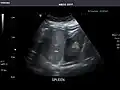

Spleen -

Spleen: Normal in size.